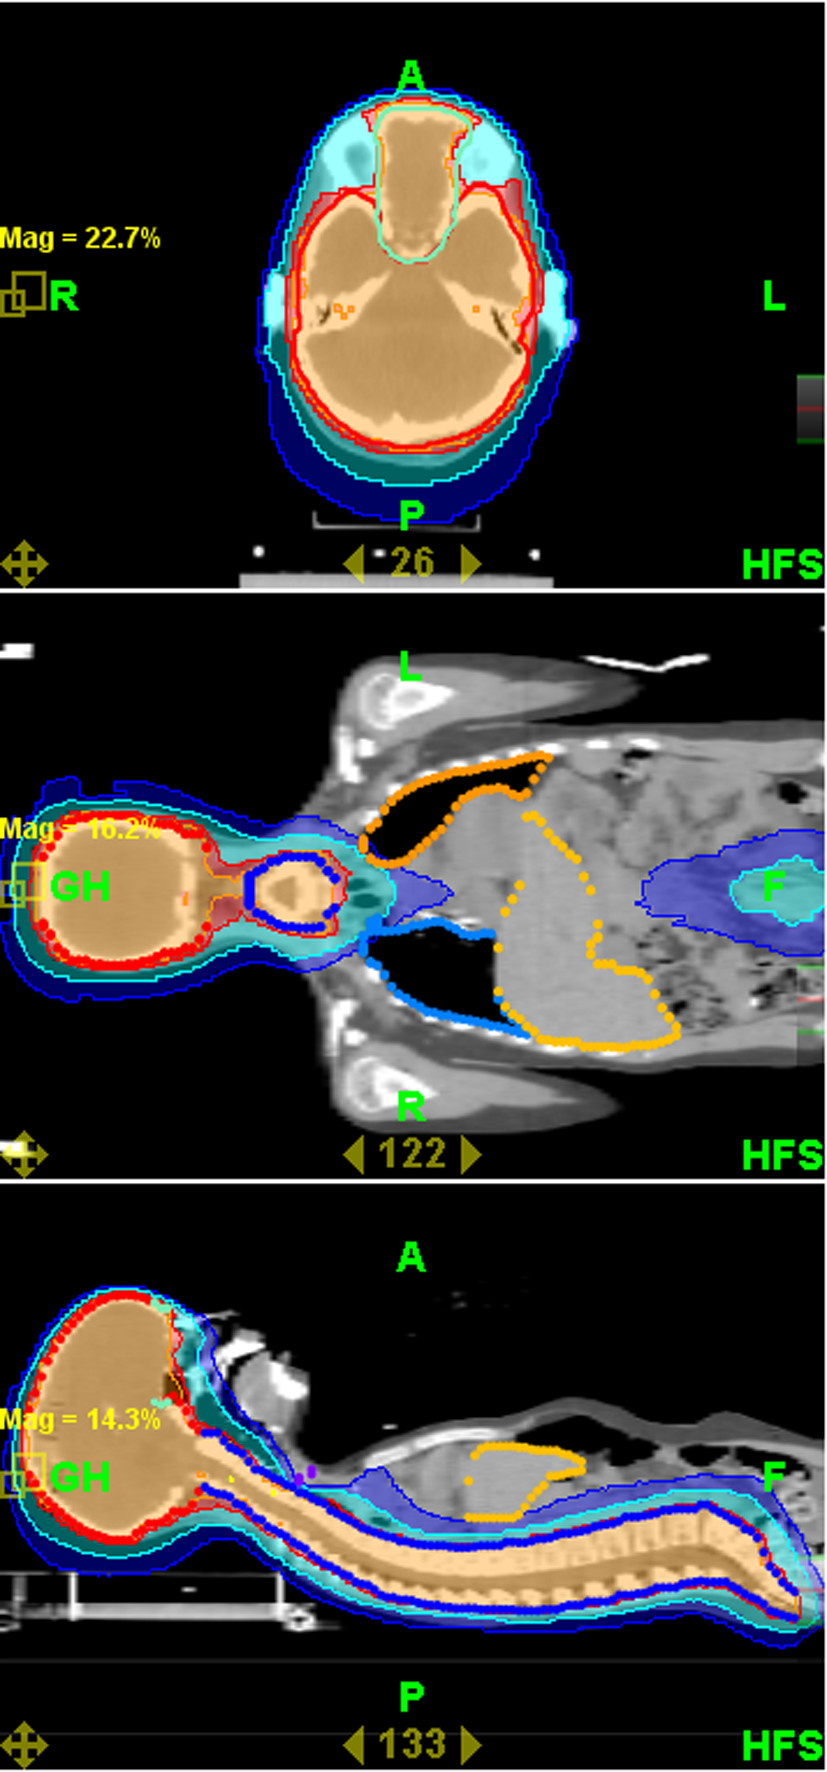

Mean coverage index for entire group of patients and all PTVs was 0,82 ± 0,13. Mean homogeneity index was 1,07 ± 0,02. Mean PTV doses, coverage and homogeneity indexes for selected challenging cases or groups of patients are presented in Table 3. Even for challenging cases of craniospinal irradiation and extended thoracic and abdominal volumes irradiation coverage and homogeneity of delivered dose were acceptable. Mean doses for selected OARs are presented in Table 4. It shows that substantial sparing of critical structures was achieved in all patients although major variability in OARs mean doses in this very heterogeneous patient population is evident. In Figures 2 and 3 examples of treatment plan for medulloblastoma and perineal rhabdomyosarcoma with metastases to inguinal nodes are presented.

Figure 3 Thumb

Figure 3. Dose distribution for perineal rhabdomyosarcoma.